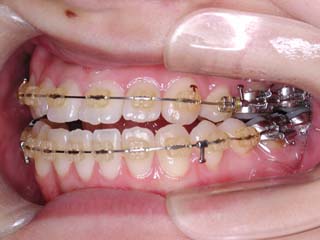

主訴:上の歯が出ている

診断名:顎関節症、上顎前突、叢生を伴う開咬

年齢:20歳

使用した主な装置名:TPB、マルチブラケット装置

抜歯/非抜歯および抜歯部位:抜歯(上顎左右第一小臼歯、下顎左右第二小臼歯)

治療期間:動的処置2年3か月、経過観察3年

費用の目安:保険適応 自己負担金として30~50万

リスク、副作用:外科手術によるリスク、マルチブラケット治療に伴う歯根吸収など偶発症が発生するリスクがある。

比較的強い叢生と、下顎の劣成長を伴う開咬が見られます。成長を終了した永久歯列ですので、骨の大きさのズレへのアプローチは大きく別れる所です。程度が小さければ、歯の傾きで補うように解決しますし、大きなズレであれば、外科的に骨のズレを改善する治療が選択されます。垂直的な問題はその他の不正咬合と比較して、解決が極めて困難な事が多いです。治療後の後戻りが頻繁に見られる不正咬合ですので、外科矯正での改善が望ましい場合も多いでしょう。

術前矯正の仕上げにスプリント治療を行った方が良い場合が多いです。現在、当院での治療では、術前に3か月のスプリント治療を必須にしております。せっかく手術までしてかみ合わせの位置を合わせようとしているのに、顎の関節の位置がずれていたらどうなるでしょう。顎の関節は往々にして顎の大きさのズレをカムフラージュするような偏位を示すので、術後にじわじわと後戻りしているような現れ方で、ズレが見えてくるのでは?このスプリント治療を徹底できたケースでは術後の安定性が極めて高いと感じています。

外科手術は、上顎のインパクションのみをLeFort1にて行いました。